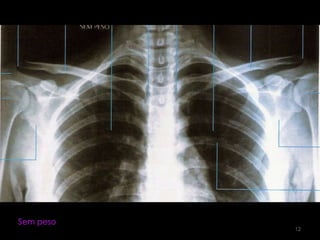

Incidência AP: Articulação acromioclavivular  bilateral (com e sem peso) 10

11

Sem peso12